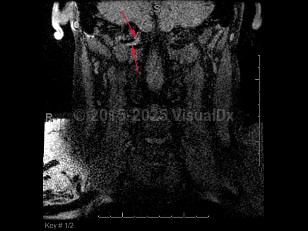

Vertebral artery dissection

Vertebral artery dissection (VAD) is splitting of the vertebral artery vessel wall, which can result in intramural hemorrhage / thrombus and expanding hematoma formation. This can lead to vessel occlusion or thromboembolism causing cerebellar and brainstem ischemia. Compromise of the vessel wall can also lead to subarachnoid hemorrhage. It is most commonly seen after a head or neck injury, including spinal manipulation, although it can occur spontaneously. It is an important cause of stroke in younger patients (under 50 years). The incidence of stroke in VAD has been estimated at 1%-8%.